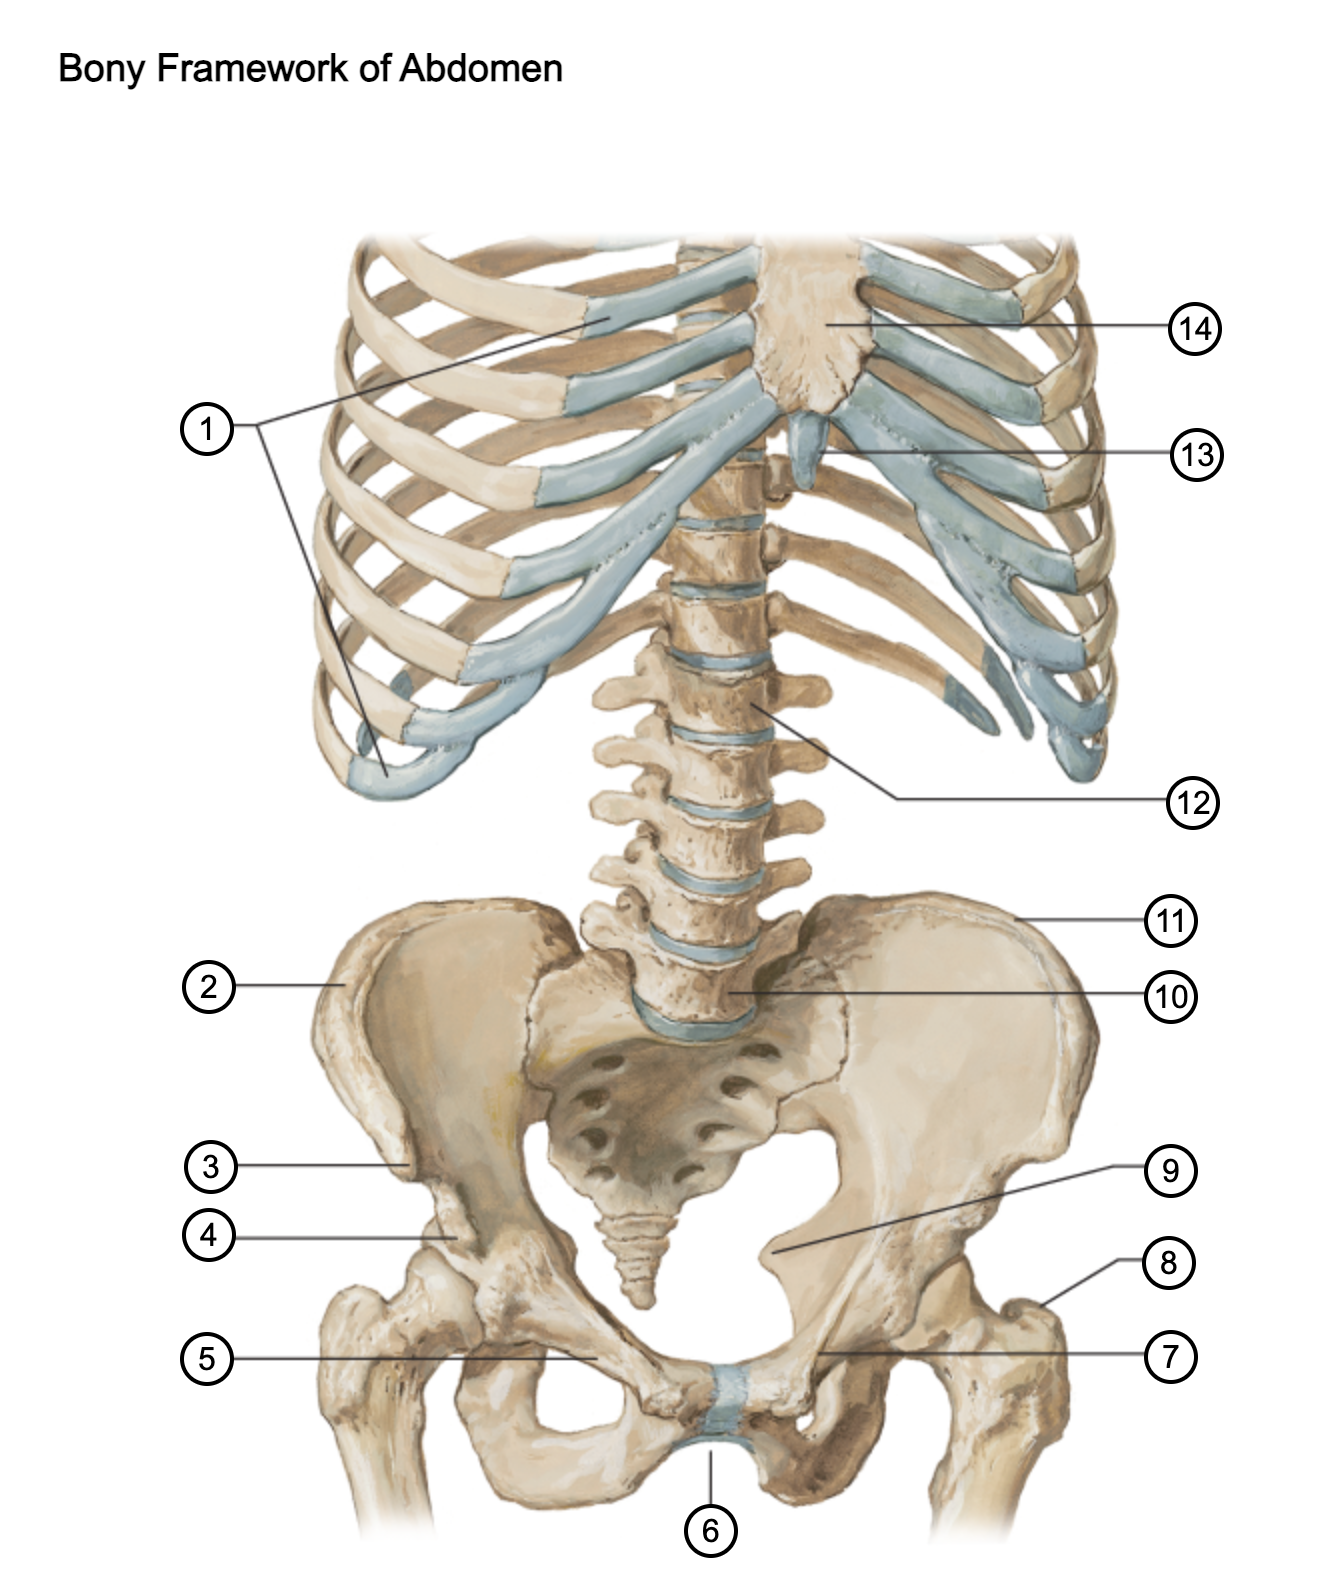

1

costal cartilages

2

iliac crest

3

anterior superior iliac spine

4

anterior inferior iliac spine

5

superior pubic ramus

6

pubic arch

7

pecten pubis

8

greater trochanter

9

ischial spine

10

L5 vertebra

11

iliac crest

12

L1 vertebra

13

xiphoid process

14

body of sternum